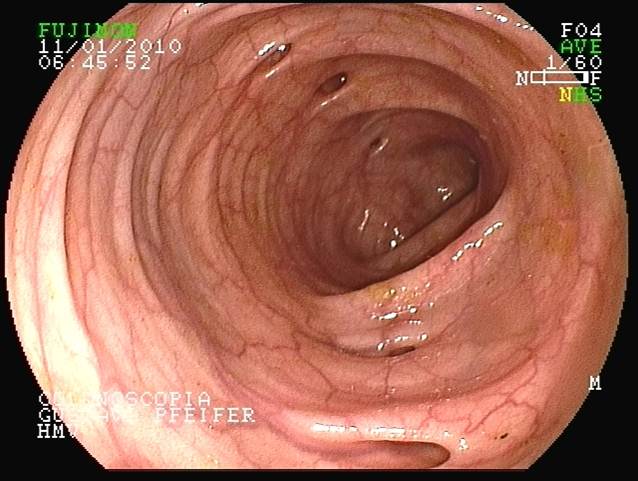

Colonoscopia: As setas indicam as áreas dos Divertículos.